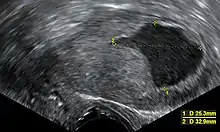

Transvaginal ultrasonography showing a uterine fluid accumulation in a postmenopausal woman.

• Accumulation of fluids other than blood or of unknown constitution. One study came to the conclusion that postmenopausal women with endometrial fluid collection on gynecologic ultrasonography should undergo endometrial biopsy if the endometrial lining is thicker than 3 mm or if the endometrial fluid is echogenic. In cases of a lining 3 mm or less and clear endometrial fluid, endometrial biopsy was not regarded to be necessary, but endocervical curettage to rule out endocervical cancer was recommended.[23]